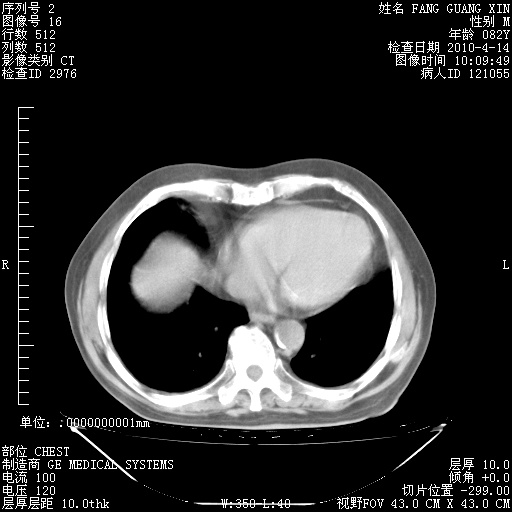

肺部CT平扫未见异常。